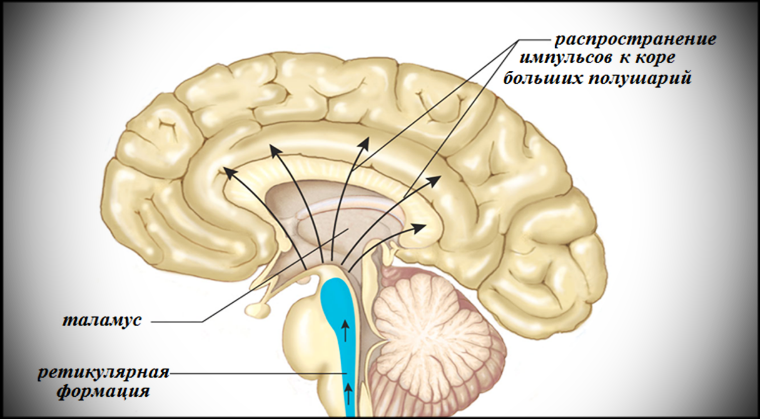

1) Ретикулярная формация – это сложная сеть нейронов, расположенная в центральной части ствола мозга (довольно маленькая по сравнению с большими полушариями или мозжечком). Считается одной из наиболее древних его частей, так как появилась на ранних этапах эволюции мозга. Критически важна в регуляции основных жизненно важных функций, таких как дыхание, сердцебиение, поддержание состояния бодрствования и перехода между сном и бодрствованием. Действует как фильтр для сенсорных сигналов, препятствуя перегрузке мозга информацией и может регулировать передачу болевых сигналов к мозгу.